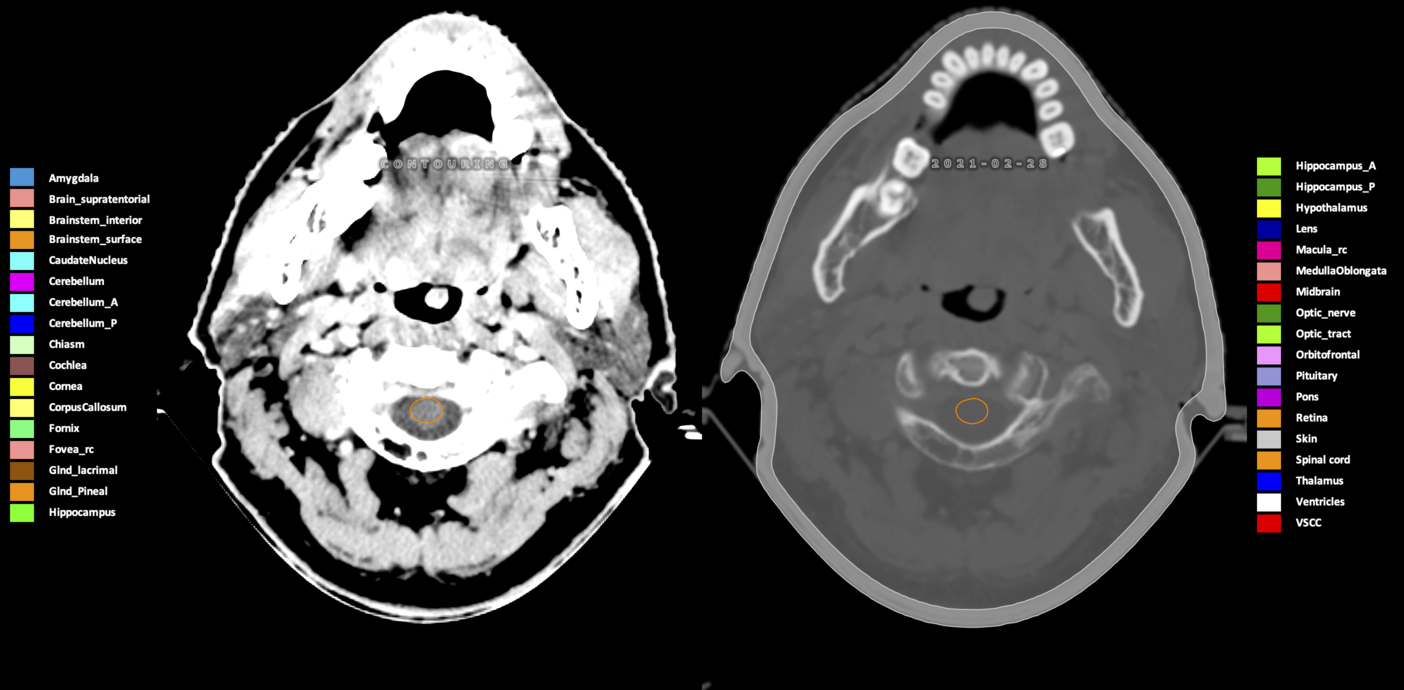

Included are all OARs known to be relevant for radiation-induced toxicity in neuro-oncology: brain, brainstem (midbrain, pons, medulla oblongata), chiasm, cerebellum (anterior & posterior), cochlea, cornea, hippocampus (anterior & posterior), hypothalamus, lens, lacrimal gland, optic nerve, pituitary, skin, and vestibular & semicircular canals. To further facilitate research on cognition, vision and radiological changes after irradiation of the brain, potential clinically-relevant OARs are included: amygdala, caudate nucleus, cerebellum (anterior & posterior), corpus callosum, fornix, macula, optic tract, orbitofrontal cortex, periventricular space (PVS), pineal gland, and thalamus.

Three-dimensional delineation of the 25 consensus OARs for neuro-oncology are shown on CT (WW/WL 120/40, 3000/600), 3T MR images, (T1Gd, T2FLAIR 1mm) and 7T MR (MP2RAGE 0.7 mm). All are presented in transversal, sagittal and coronal view.